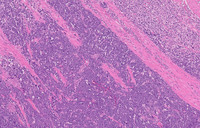

Figure 1: Low power H&E Morphology of Double Hit Lymphoma

Low power image (on the left) demonstrates circumscribed infiltrate of cells within the lamina propria and extending through the full thickness beyond the muscularis propria in some areas. At higher power (pictured on the right), the infiltrate is diffuse.